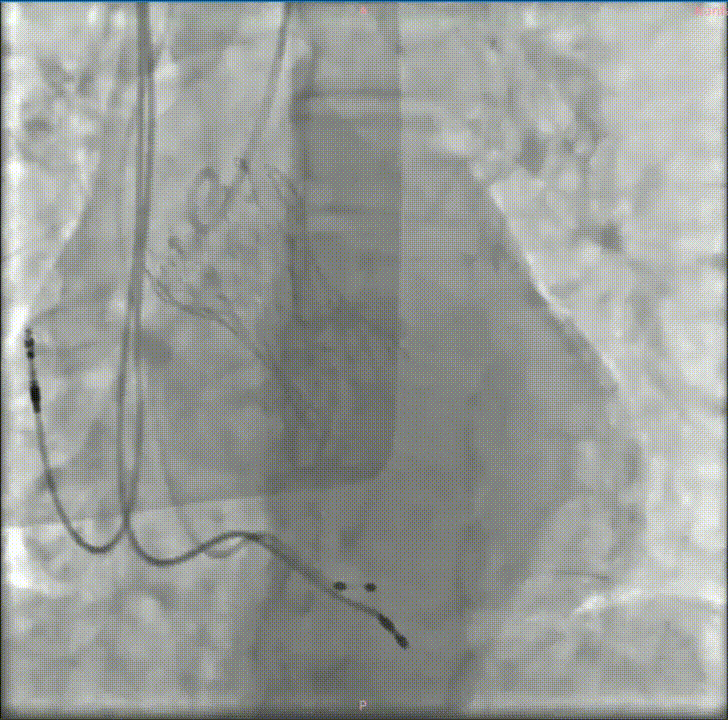

经过充分的术前评估和准备,修建成教授带领由医院心内、超声、麻醉、放射等多学科成员组成的手术团队,开始了这台TAVR手术。

穿刺、置管、跨瓣、扩张、释放瓣膜、测压、检测、拔管、手术结束……当天的DSA手术台上,修建成教授和团队有条不紊地完成着每一个步骤。术中的每一个步骤、每一个节点、每一个动作,团队每位成员都十分娴熟。最终成功在预定位置精准植入瓣膜。

深度评估

释放后造影

后扩

瓣膜植入后立即进入工作状态,术后造影显示瓣膜工作状态良好,无瓣周漏及明显跨瓣压差;冠脉无阻挡,无传导阻滞

采访中,修建成教授欣慰地分享了手术效果:“手术之后的结果也验证了我们术前的分析和想法。从影像学结果分析来看,我们把瓣周漏减少到非常低的水平,同时瓣膜的扩张、展开都非常好,可以说达到一个非常理想的结果。”